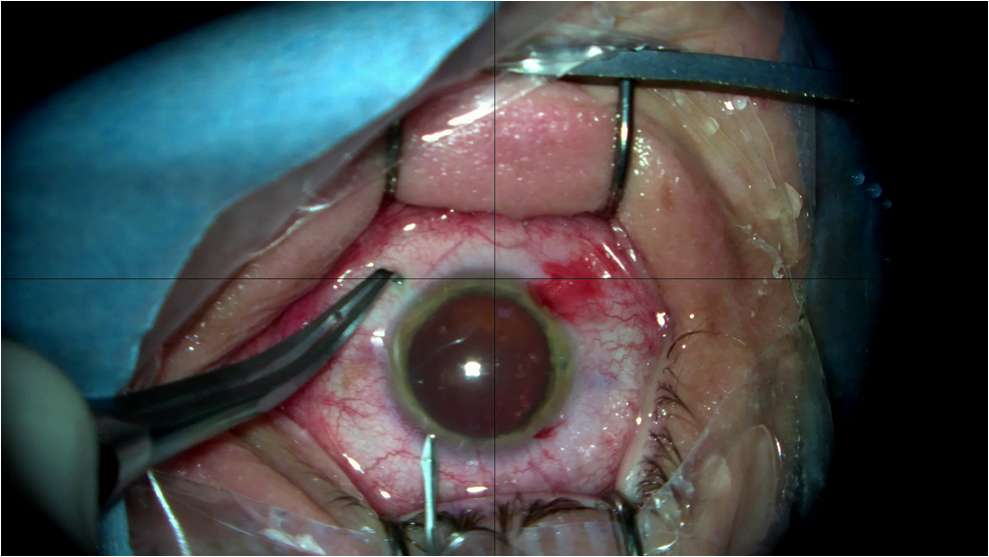

Как проходит операция?

Эта малотравматичная, быстрая и безболезненная хирургическая процедура проводится в несколько этапов:

Проводится местная капельная анестезия. Пациент при этом в сознании, но боли не чувствует.

Врач выполняет микроразрез роговицы около 2,5 мм, через который вводит специальный гелеобразный раствор (защищает внутренние структуры глаза и создает пространство для линзы).

Факичная пресбиопическая ИОЛ в свернутом виде аккуратно помещается внутрь задней камеры. Там она разворачивается и фиксируется в правильном положении, «расправляясь» за радужкой.

Позиционирование, вращение и манипулирование факичной линзой в задней камере является сложной задачей. Очень удобно, что торическая (астигматическая) ФИОЛ не требует вращения. Линза располагается горизонтально, а торическая ось автоматически оказывается в правильном положении, поскольку необходимая ось предварительно изготавливается в оптике (и гиперметропическая, и миопическая). Это сильно повышает безопасность!

Весь процесс на одном глазу занимает в среднем 5–7 минут. Операция выполняется амбулаторно. В клинике пациент проводит 3–4 часа. Оба глаза оперируются в один день, как при лазерной коррекции.